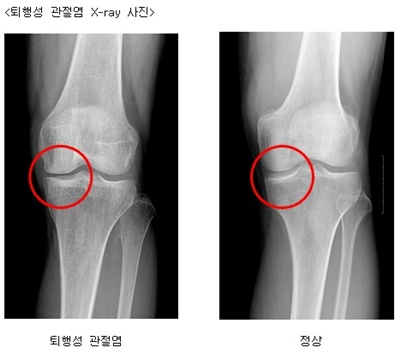

<퇴행성 관절염 X-ray 사진>

퇴행성 관절염 정상